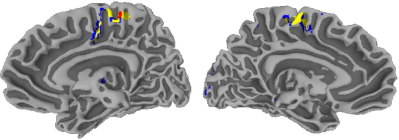

As before, we run the -means algorithm to termination, with initializations using the methods in Section II-C, for . The jump statistic identified the three-groups solution as the optimal partitioning. The resulting groups are displayed in Figure 8 separately, for each of the eleven

experiments. The first group (denoted by red) consists of 235 voxels whose average mean -score is 10.31, the second (yellow) group has 965 voxels with average mean -score 6.83, and the third (blue) group includes 1627 voxels with an average mean -score of 4.96. The first group is where the activation is most emphatic and is almost entirely in the right primary motor cortex (M1), the ipsi- and contra-lateral pre-motor cortices (pre-M1), and the supplementary motor cortex (SMA). The other two groups of voxels represent two different kinds of milder activation and are primarily located in the right pre-SMA, and interestingly also in the left M1, pre-M1, and the SMA. This last observation is an interesting finding and is suggestive that activation in a right-hand dominant male is also associated in the left hemisphere of the brain even when it is the non-dominant hand that is active in performing a task. It is important to note that following a whole data strategy in this experiment would not have been able to identify this additional finding because almost all the 156 voxels that have non-thresholded -scores for all eleven replications (that is, having no missing values) are in the right hemisphere. Our application here also demonstrates an important approach to amalgamating the results from different fMRI activation studies.